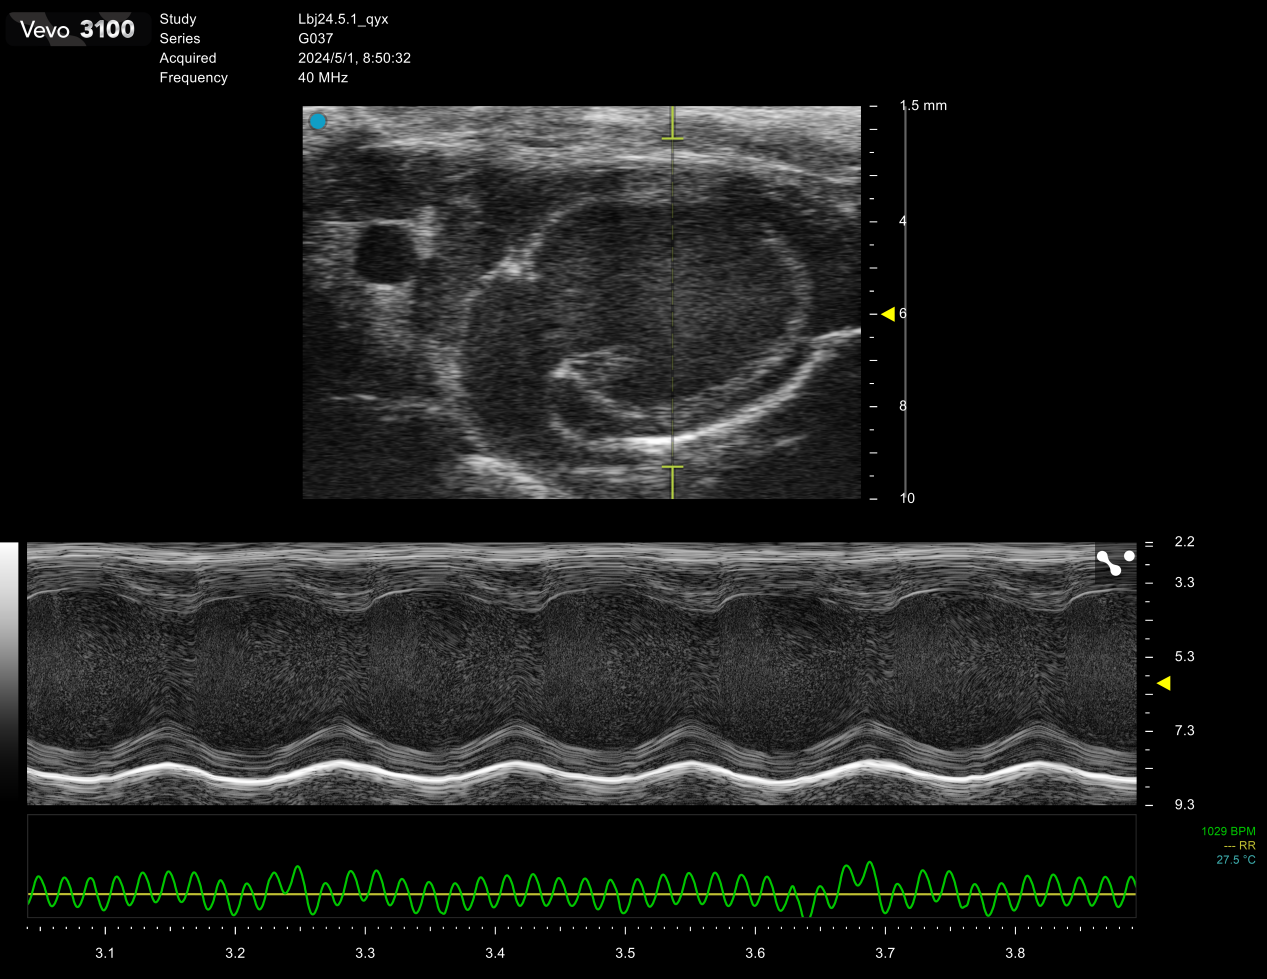

SiliconWave 60高频超声

1.心脏疾病常见的如心肌梗塞,心肌肥厚,心衰及高血压等。

2.血管疾病比如观测动脉粥样硬化斑块的形成与消融,血栓的形成与消融。

3.肿瘤动态监测肿瘤体积的研究可追踪肿瘤随时间的生长与转归。

4.肝脏疾病对脂肪肝、肝硬化、肝肿瘤等进行探测和定位,追踪病灶的进展。

5.胚胎发育可以实现从胚胎发育第五天开始到新生再到成年小鼠的发育研究,检测胎盘、脐带血流,分析小动物心脏发育相关重大遗传性疾病的发生、发展的规律及治疗方案等。